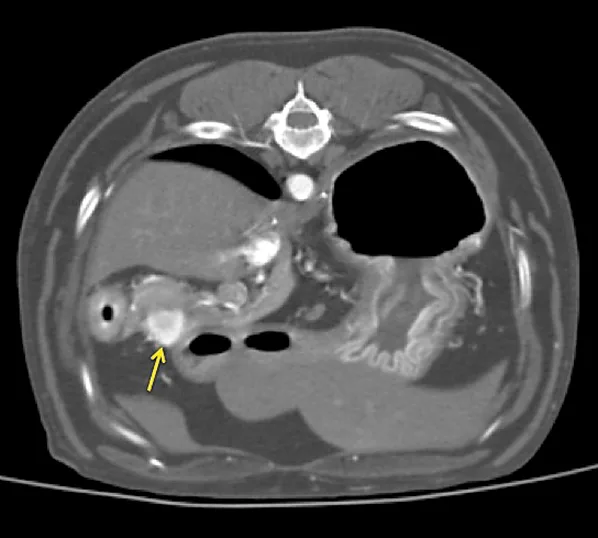

A thoracoabdominal dual-phase CT scan was performed with the goals of further evaluating the pancreatic nodule, ruling out obvious metastatic disease, and planning for possible surgery. The CT scan revealed a 1.8 × 2.6-cm nodule in the body of the pancreas that demonstrated marked neovascularization in the early arterial phase and mild peripheral contrast enhancement relative to the remainder of the pancreas in the main arterial and portal phase scans (Figure 2). A strong contrast-enhancing liver nodule was noted in the arterial phase of the CT angiogram (Figure 3). Other hepatic nodules noted on ultrasound were not visualized in the arterial or mixed portal/venous angiographic phases. No evidence of nodular pulmonary metastasis was evident.